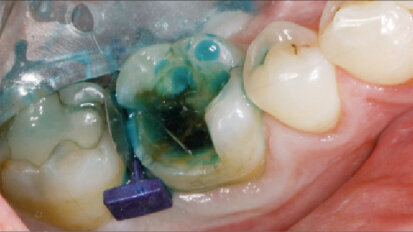

Klinické použití nového zatékavého podkladového materiálu pro přímé a nepřímé výplně

Poslední vývoj v oblasti kompozitních materiálů a vazebných technologií umožnil jejich běžné ...